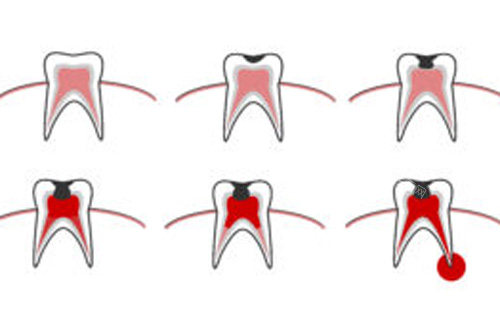

补牙材料价格

儿童玻璃材料补牙80元起(适合乳牙),

国产树脂补牙150元起(后牙通用),

进口树脂补牙280元起(色泽更自然)。